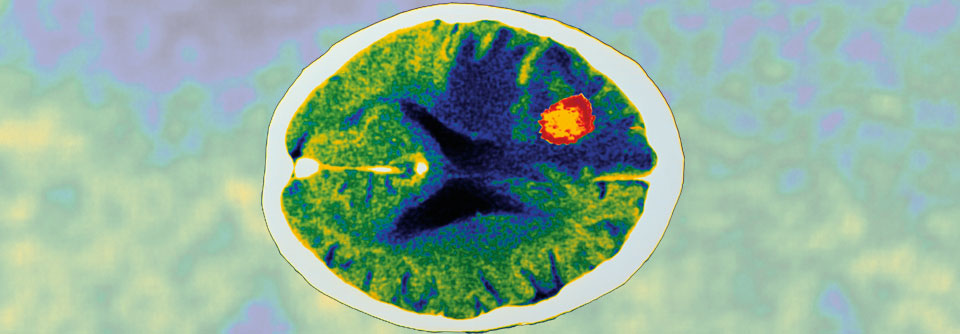

Man steht gerade mitten im Leben, die Karriere nimmt richtig Fahrt auf – und plötzlich die Diagnose: Hirntumor. Dank moderner Therapien stehen die Chancen auf Heilung mittlerweile gut, doch die Rückkehr in den Beruf gestaltet sich vor allem in den ersten beiden Jahren schwierig. Besonders für Frauen.

Ein Jahr nach der Diagnose eines Low-Grade-Glioms ist weniger als ein Drittel der Betroffenen wieder voll berufstätig, nach zwei Jahren knapp die Hälfte. Zu diesem Schluss kommt eine schwedische Registerstudie. An dem langsam wachsenden Hirntumor erkranken typischerweise Menschen im mittleren Erwachsenenalter, erläutert die Neuropsychologin Isabelle Rydén von der Universität Göteborg und Kollegen.